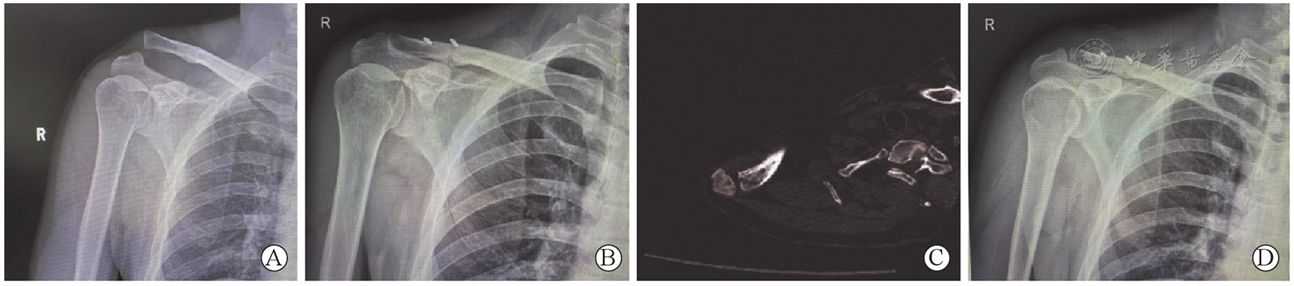

图3 关节镜下无喙突骨隧道悬吊式固定治疗急性右肩锁关节脱位手术前后影像。图A为右肩术前正位X线片,示RockwoodⅢ型肩锁关节脱位;图B为右肩术后第1天X线片显示肩锁关节复位良好;图C为术后1个月肩关节CT,示右肩锁关节前后向复位良好;图D为术后半年随访X线片,示右肩锁关节仍在位

Figure 3 Pre-and postoperative images of acute right ACJD (acromioclavicular joint dislocation) treated with arthroscopic suspension fixation without coracoid bone tunnel. A is X-ray image at anteroposterior view of right shoulder before surgery, showing Rockwood typeⅢ acromioclavicular joint dislocation;B is X-ray image at anteroposterior view of right shoulder one day after surgery, showing satisfactory reduction of the acromioclavicular joint;C is CT image of right shoulder one month after surgery, showing satisfactory anteroposterior reduction of the acromioclavicular joint;D is X-ray image at anteroposterior view of right shoulder six months after surgery, showing the acromioclavicular joint remained in position